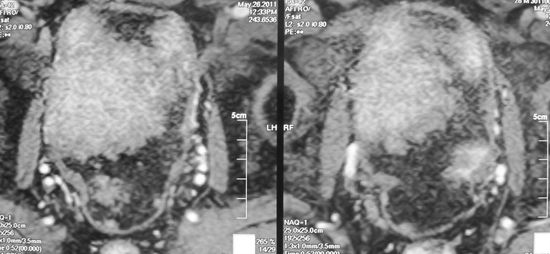

Скелилитизация наружных подвздошных сосудов с сохранением семевыносящего протока

Обтураторная лимфодиссекция